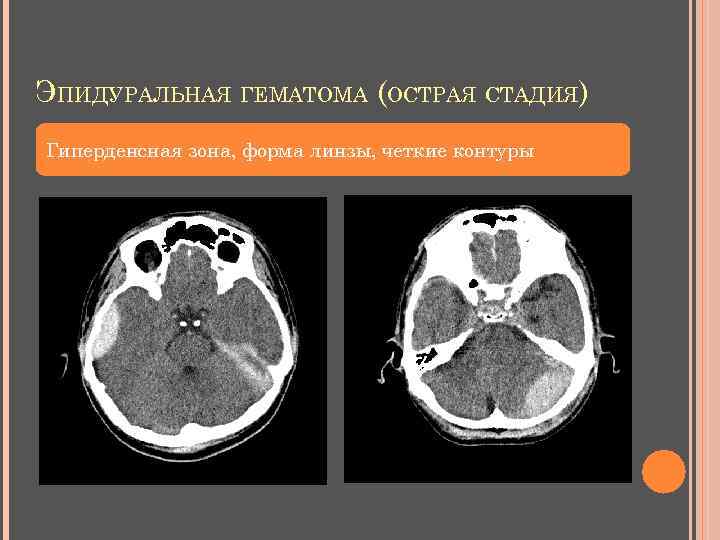

ЭПИДУРАЛЬНАЯ ГЕМАТОМА повреждение ветвей оболочечных артерий (85% - средней оболочечной артерии) повреждение диплоических вен повреждение венозных синусов локализация – височно-теменная область Клиника: неотложное состояние, которое может быстро привести к летальному исходу тошнота, рвота, головная боль, потеря сознания м. б. стремительное ухудшение состояния анизокория или внезапная утрата реакции зрачков (поздний симптом) пациенты часто на ИВЛ

ЭПИДУРАЛЬНАЯ ГЕМАТОМА КТ: гиперденсная зона по контуру кости (+70…+80 HU) форма двояковыпуклой линзы прилежит к кости внутренний контур четкий, ровный не пересекает линии швов «масс-эффект» - смещение срединных структур меньше толщины гематомы структура зависит от давности возникновения длина: ширина = 5: 1 м. б. перелом кости в дне гематомы

ЭПИДУРАЛЬНАЯ ГЕМАТОМА (ОСТРАЯ СТАДИЯ) Гиперденсная зона, форма линзы, четкие контуры